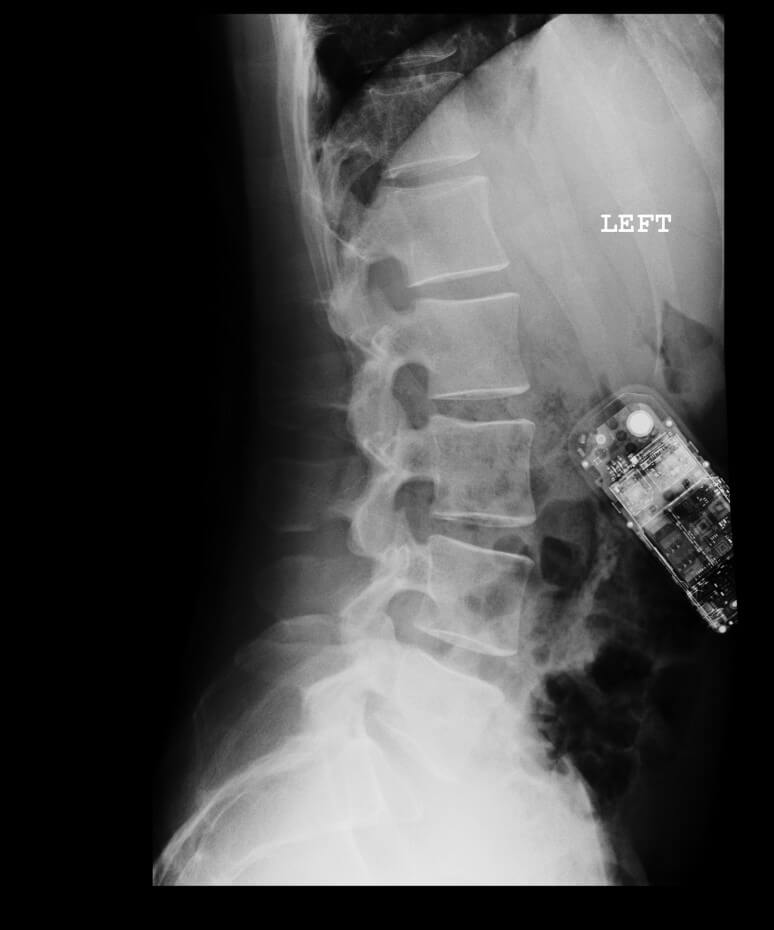

I will be the film composer for Rebecca Doppelt’s next film Bugbaby. I was on set today to get a head start by observing her directing, which was fun. I crashed my motorcycle on the way home, which was not. I was hospitalized with a serious concussion and I lost 24 hours of my memory, but I’m okay and the film is going to be great.